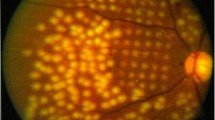

Subretinal fibrosis is the most common natural sequela of MNV and causes damage to the photoreceptors, RPE, and choriocapillaris, resulting in irreversible loss of central vision (Bressler 1988; Wong et al. 2008). Cheung et al. reported an increase of subretinal fibrosis in patients with treatment-naive nAMD from 13.0 to 37.8% within 1 year (Cheung et al. 2019). Histopathological studies show that the severity of photoreceptor damage is proportional to the size of subretinal fibrosis in AMD eyes (Green and Enger 1993), supporting the clinical observation that subretinal fibrosis is the most important predictor of final visual acuity (Cheung et al. 2019). The risk of eyes with nAMD to develop subretinal fibrosis despite ongoing anti-VEGF therapy is reported to be 45% by 2 years (Daniel et al. 2014) and 41% by 10 years (Teo et al. 2020). This is of particular concern because eyes with subfoveal fibrotic scarring after anti-VEGF treatment have the worst prognosis in terms of visual acuity after anti-VEGF treatment (Daniel et al. 2014). Therefore, alternative therapeutic strategies are needed to circumvent the dilemma of inhibiting vessel growth but risking the promotion of scar formation at the same time. Clinically, subretinal fibrosis can be evaluated by funduscopy, fluorescein angiography, and polarization-sensitive optical coherence tomography (PS-OCT) and categorized into fibrotic and non-fibrotic scars (Roberts et al. 2019). While fibrotic scars are characterized as raised clusters of white or yellowish tissue that are well-defined in shape and appear solid on funduscopy, non-fibrotic scars are typically flat, unpigmented lesions with varying amounts of peripheral dark pigmentation. Fibrotic and non-fibrotic scars can both develop with ongoing anti-VEGF therapy, occurring in 24.7% and 20.6% of cases with nAMD after 2 years of therapy, respectively (Daniel et al. 2014). However, it is unclear whether these clinical subtypes of subretinal fibrosis represent pathophysiologically distinct entities or converging disease stages.

There are a number of risk factors for the occurrence of subretinal fibrosis. In general, eyes are more likely to develop subretinal fibrosis during the course of anti-VEGF treatment if they have type 2 MNV (classic CNV), blocked fluorescence on fluorescein angiography (FA) as an indication of bleeding, large basal lesions, increased retinal thickness, foveal subretinal fluid, and subretinal hyperreflective material (SHRM) under the foveal centre at baseline (Fig. 2) (Bloch et al. 2013; Daniel et al. 2018; Teo et al. 2020). It has been proposed that MNV type 2, which penetrate the RPE layer and grow in the subretinal space, are more likely to contain damaged and scattered RPE and thus be more likely to progress to fibrosis than type 1 MNV, which are usually confined to the space beneath the RPE (Ishikawa et al. 2016). Furthermore, several studies suggest that intra-retinal or subretinal haemorrhage, which can result in blocked fluorescence on FA (Fig. 1), is associated with an increased risk of fibrovascular scarring (Scupola et al. 1999; Daniel et al. 2018; Teo et al. 2020) suggesting that cellular and molecular components of the blood can exaggerate scar formation. The detection of SHRM by optical coherence tomography (OCT; Fig. 1) correlates with the formation of a retinal scar and is considered a diagnostic biomarker for fibrosis in nAMD (Casalino et al. 2020). The exact molecular and cellular composition of SHRM is unknown, but it is assumed to be a mixture of fibrovascular tissue, haemorrhage, lipids, fibrin, and immune cells, all of which show similar reflectivity on OCT. Also, a longer interval between diagnosis and treatment (Bloch et al. 2013) and persistent cystoid changes are associated with an even higher risk of developing fibrosis compared to persistent diffuse subretinal fluid (Gianniou et al. 2015). Subretinal fibrosis in patients with nAMD is associated with higher plasma levels of C3a, C4a, and C5a (Lechner et al. 2016); lower serum 25-hydroxyvitamin D concentrations (Singh et al. 2013; Kim and Park 2018); and a higher percentage of circulating CD4 + T-cells as compared to nAMD patients without subretinal fibrosis (Lechner et al. 2015). Interestingly, the incidence of scar formation is relatively low in type 3 MNV lesions which originate from the retinal vasculature and may therefore be more confined to the neurosensory retina without affecting the RPE to the same degree as type 1 and type 2 MNV (Chang et al. 2016; Kim et al. 2018). To date, no genetic and epigentic alterations have been found which predispose an individual to the formation of subretinal scarring. In particular, no association was found between subretinal fibrosis and the common single nucleotide polymorphisms (SNPs, complement factor H, age-related maculopathy susceptibility 2, complement component 3, and toll-like receptor 3) which are known to be strongly associated with the development of AMD (Daniel et al. 2018).